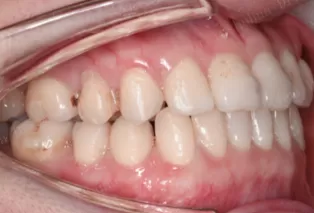

Intraoral photos